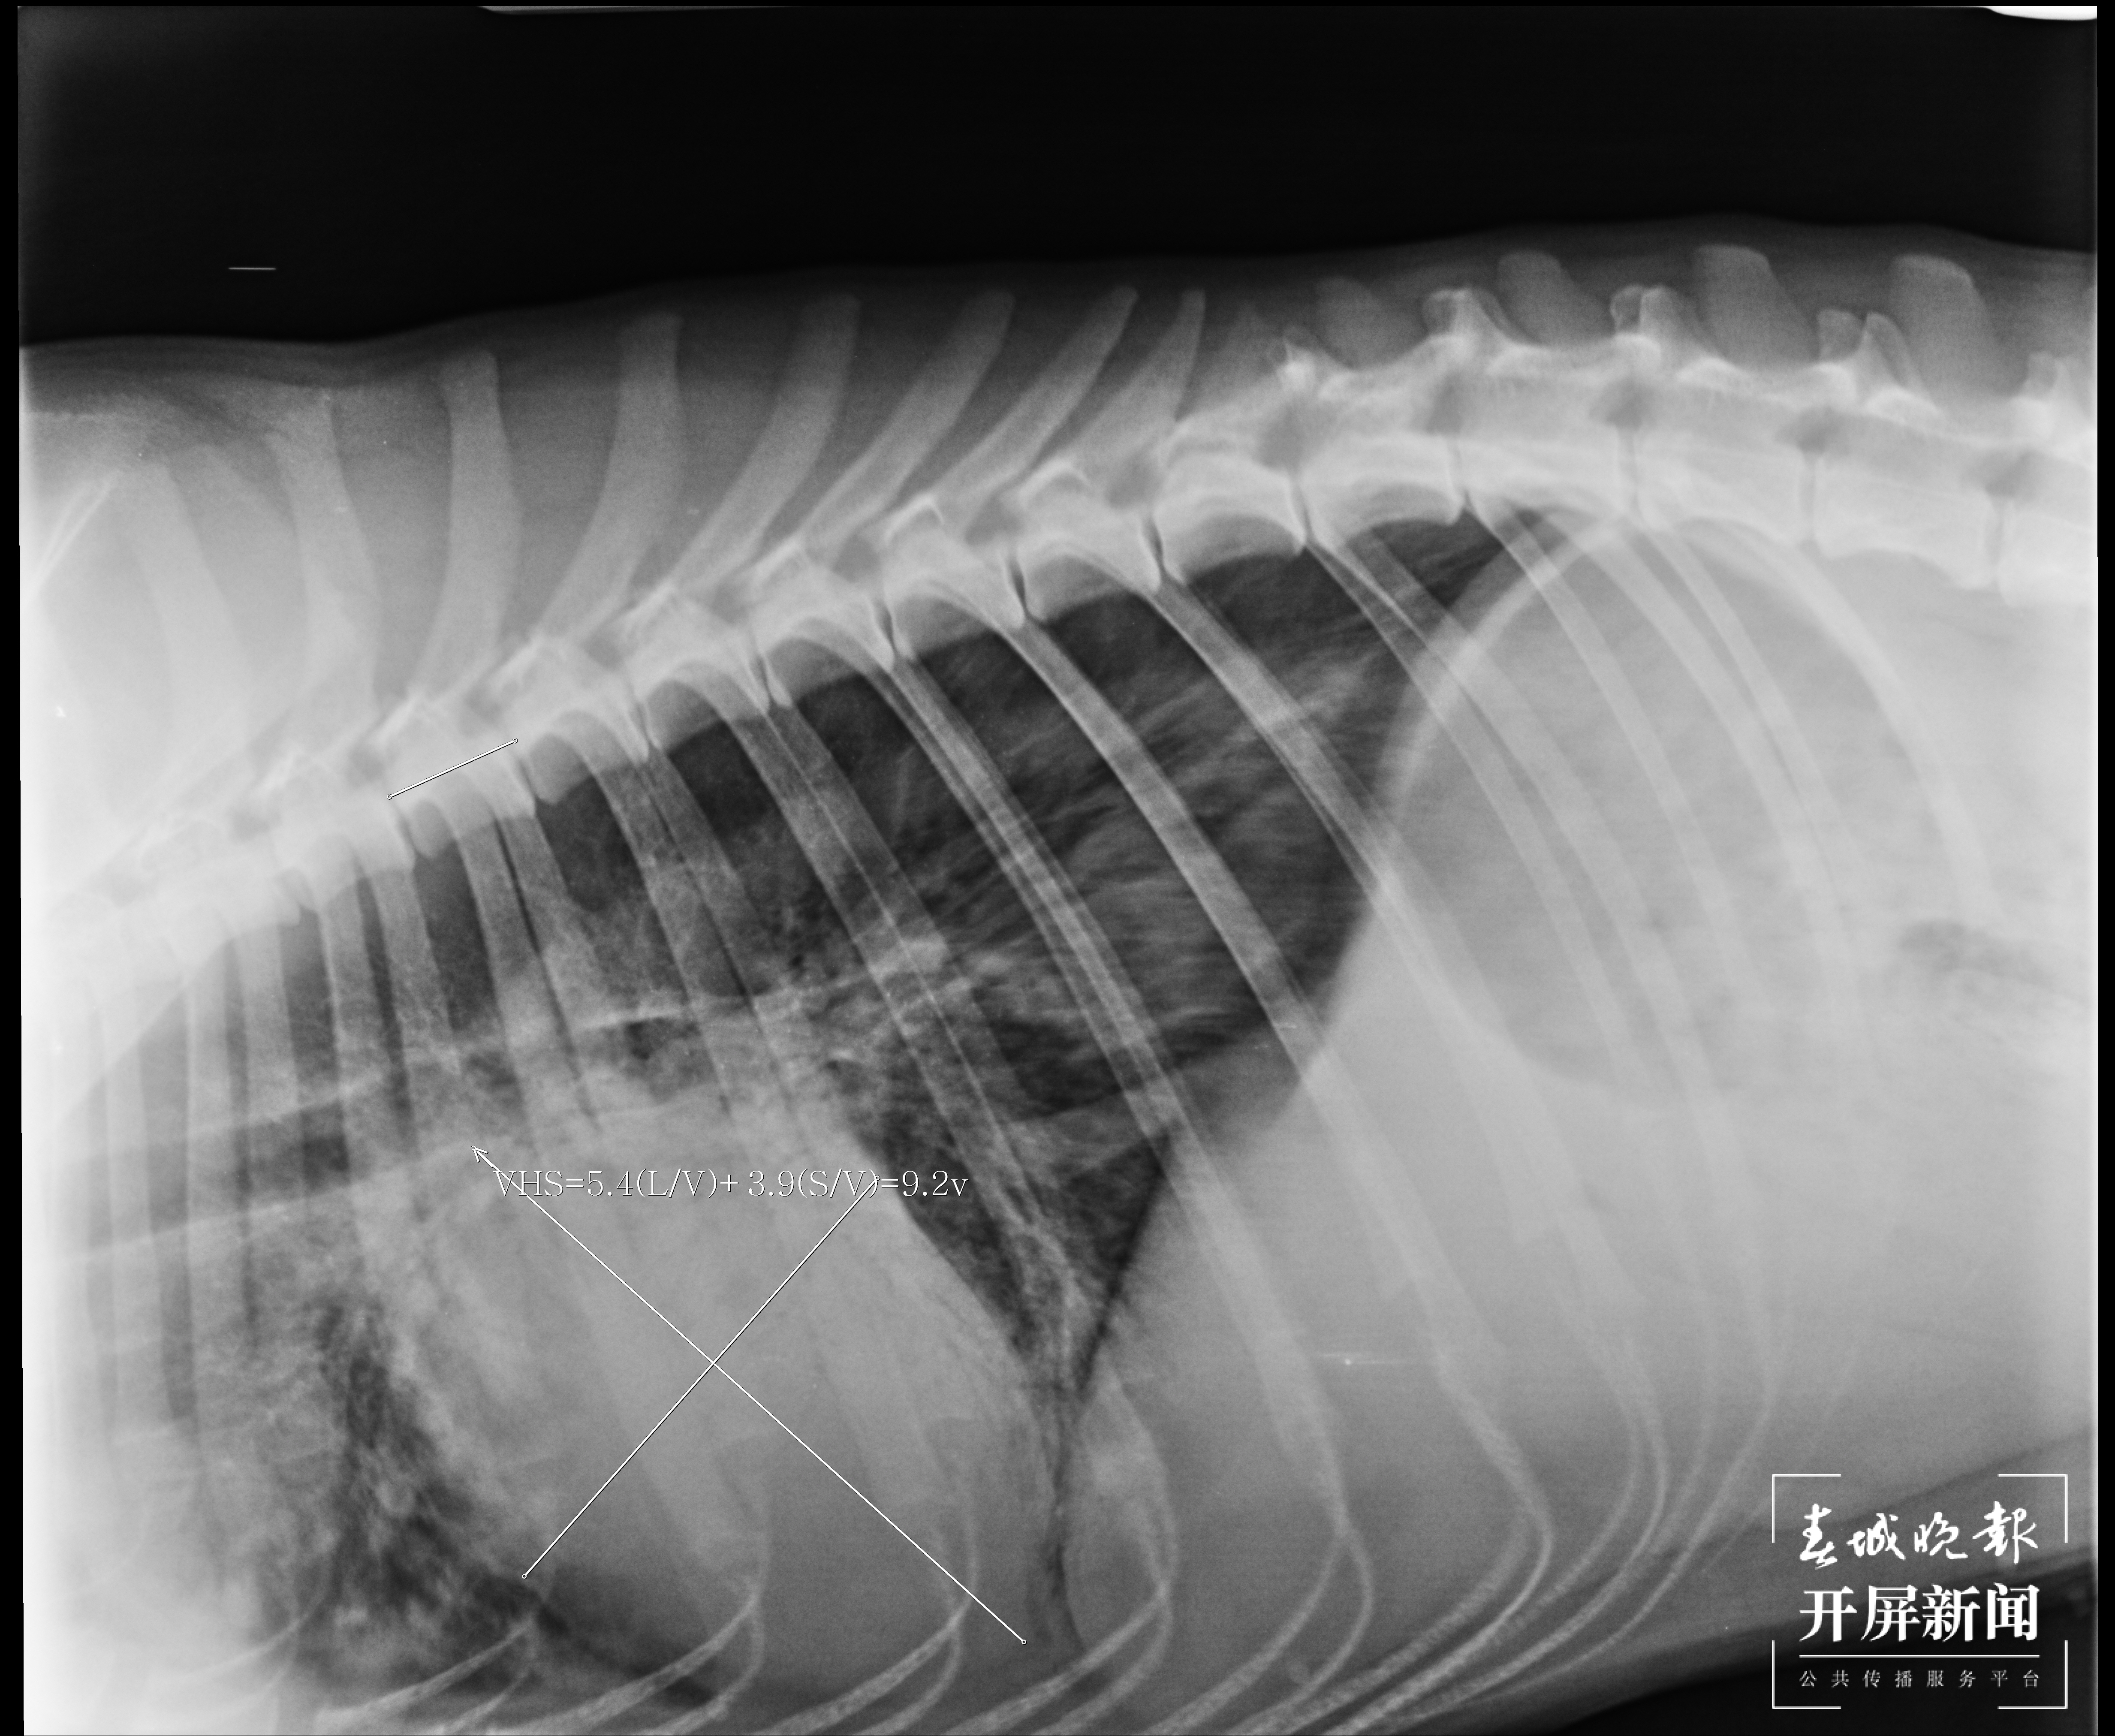

▲2月22日,CT显示心脏肿大。(受访者供图)